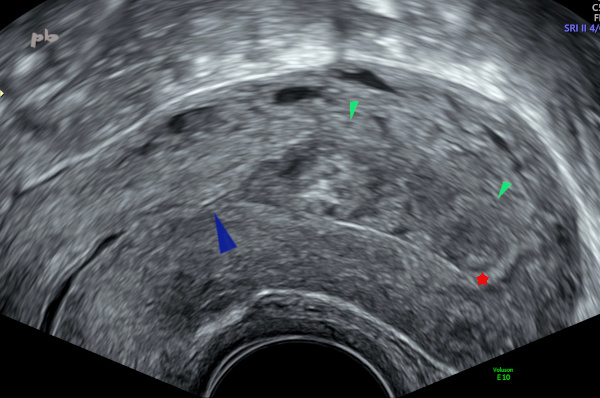

8 – Résidus trophoblastiques

Echographie – Coupe sagittale.

IVG médicamenteuse il y a 3 semaines.

Dédoublement de la muqueuse au niveau de l’orifice interne cervical (►).

Masse hétérogène dans la cavité avec effacement de l’interface endomètre – myomètre en postérieur (►). Persistance d’une bande hyperéchogène en antérieur (endomètre ou caduques ★).